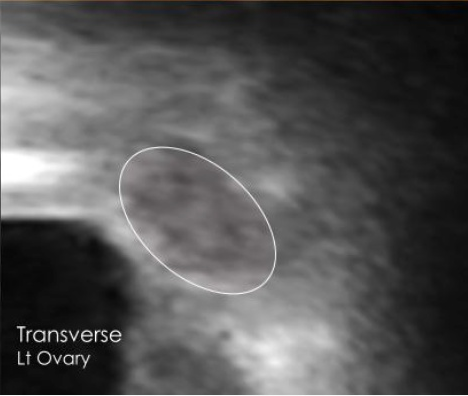

Left ovary transverse view ultrasound Left ovary sagittal view ultrasound

Bilateral Ovaries

12 antral follicles — within normal range

Normal

Both ovaries are a healthy size and shape. A total of 12 antral follicles were visible (5 on the right, 7 on the left), which is within the normal range for your reproductive health. This is a reassuring result.

Note: These images were captured at home by a user with no medical training using Chealth technology, demonstrating the quality achievable with our guided scanning system.